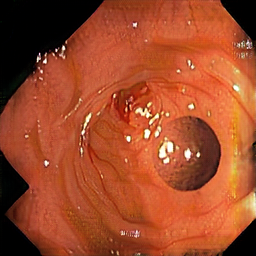

Synthetic

Real

Domain randomization